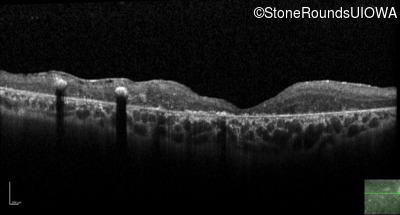

Optical Coherence Tomography - Right - 10/700 sc

Exemplar / OCT Stack